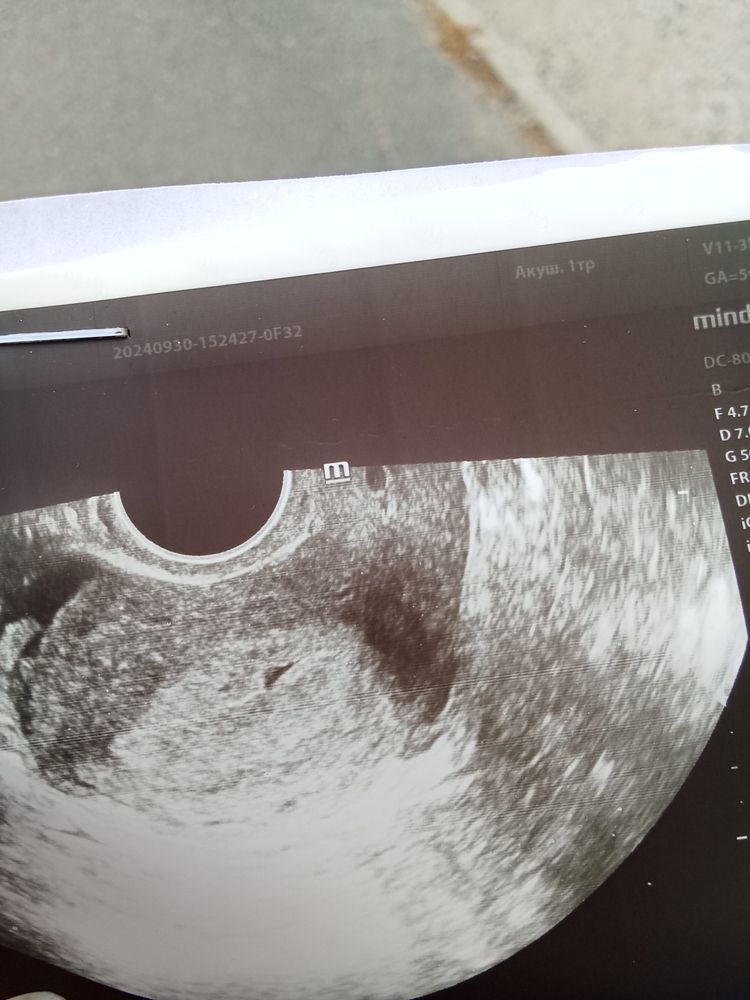

Мама индахаус, да.эндометрий 18, жт 26. Изображение Первый раз такая полость. Куча УЗИ после овуляции.

Лидия, а вот точка чёрная это что?

Мама индахаус, вот какая то полость появилась. Врач побоялась делать прогноз. Сказала через неделю посмотрим. Вот сравнение УЗИ июля и сегодня. Не было такого. И эндометрий такой впервые.обычно 12-14. В бхб было 16. А тут средняя величина 18. Изображение